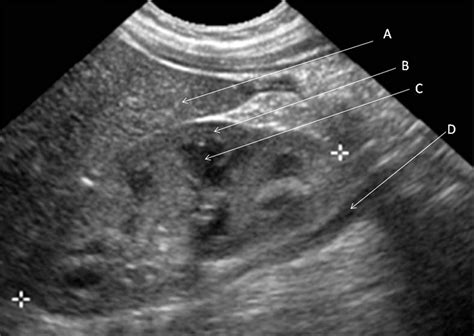

A kidney ultrasound, or sonography, uses high-frequency sound waves to create images of the kidneys, ureters, and bladder. It is frequently the first line of investigation for clinicians because it is safe, widely available, and highly effective at identifying structural abnormalities. When a radiologist reviews the images, they are looking for specific markers that indicate health versus disease.

When you receive a report stating you have a Normal Ultrasound Of Kidneys, it means that the radiologist has evaluated several specific parameters and found them to be within expected clinical ranges. The kidneys are evaluated for their size, shape, position, and internal architecture. If these elements match the standard anatomical profile for a healthy adult, the organ is considered functioning structurally as intended.

Primary areas examined during the scan include:

• Cortical Echogenicity: The brightness of the outer layer of the kidney.

• Corticomedullary Differentiation: The clear visual distinction between the outer cortex and the inner medulla.

• Size and Dimensions: Ensuring the kidneys are not too small (atrophied) or abnormally enlarged.

• Presence of Hydronephrosis: Checking for swelling caused by a backup of urine.

• Masses or Cysts: Looking for abnormal growths, tumors, or fluid-filled sacs.

The term Normal Ultrasound Of Kidneys is standardized by medical imaging professionals. During the procedure, the sonographer maneuvers a transducer over your abdomen and back, capturing images from multiple angles. The following table summarizes what clinicians identify as normal characteristics compared to potential abnormal findings.

Parameter Expected Normal Finding Potential Abnormal Finding

Kidney Size Typically 9–12 cm in length Small/shrunken (chronic disease) or enlarged

Echogenicity Less than or equal to the liver/spleen Increased (suggests parenchymal disease)

Calyceal System No dilation or collection of fluid Hydronephrosis (dilation/obstruction)

Renal Outline Smooth, regular borders Irregular, lobulated, or scarred

Fluid Presence None, unless simple benign cysts Complex masses or stones (calculi)